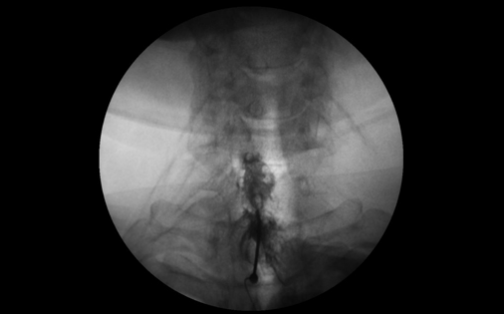

실시간 영상장치를 통해 통증의 원인이 되는 신경 뿌리를 정확하게 찾아서 약물을 주입해 염증 및 부종을 가라앉히는 치료예요.

허리뿐 아니라 목 부위에도 적용할 수 있고, 시술 시간이 짧고 회복 속도가 빠른 편이랍니다.